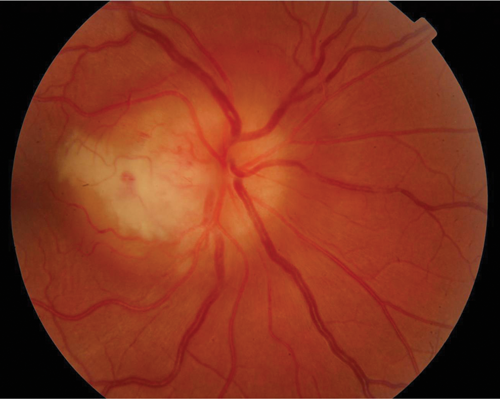

A 30-year-old Caucasian presented with the first episode of unilateral, painless visual loss in one eye upon waking. Crohn’s disease was diagnosed 18 months ago on colonoscopy after a single episode of colitis. She was on no medication. She presented with gross swelling of the optic nerve head on the right and swelling of the left optic nerve head. Vision was 6/36 on the right and 6/9 on the left.

Figure 1 (top and above): Case 2 - right and left fundus.

There was a dense right RAPD, reduction in colour vision, a large, dense unilateral, nasal scotoma, and bilateral mild vitritis. MRI showed no white matter lesions. She was treated with high dose oral steroids with a residual dense nasal field defect and central visual acuity of 6/9. This is an atypical optic neuritis which may be associated with Crohn’s disease. Here the atypical features are the absence of pain, gross optic nerve head swelling and bilateral disease. The presence of intermediate uveitis is consistent with Crohn’s disease. The MRI findings support the likelihood that this pathological process was limited to optic nerve.